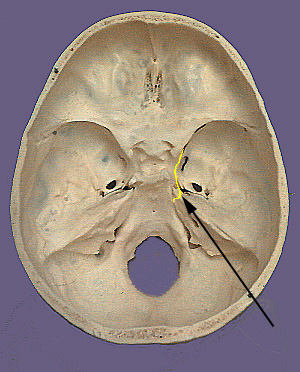

Cranium CN IV

CN IV. Trochlear Nerve

The trochlear nerve is purely a motor nerve and is the only cranial nerve to exit the brain dorsally. The trochlear nerve supplies one muscle: the superior oblique. The cell bodies that originate the fourth cranial nerve are located in ventral part of the brainstem in the trochlear nucleus. The trochlear nucleus gives rise to nerves that cross (decussate) to the other side of the brainstem just prior to exiting the brainstem. Thus, each superior oblique muscle is supplied by nerve fibers from the trochlear nucleus of the opposite side. The trochlear nerve fibers curve forward and enter the dura mater at the angle between the free and attached border of the tentorium cerebelli. The nerve travels in the lateral wall of the cavernous sinus and then enters the orbit via the superior orbital fissure. The nerve travels medially and diagonally across the levator palpebrae superioris and superior rectus muscle to innervate the superior oblique muscle.